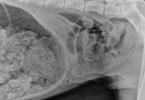

Raio X mostra tumor em gato provocado por fumo de...